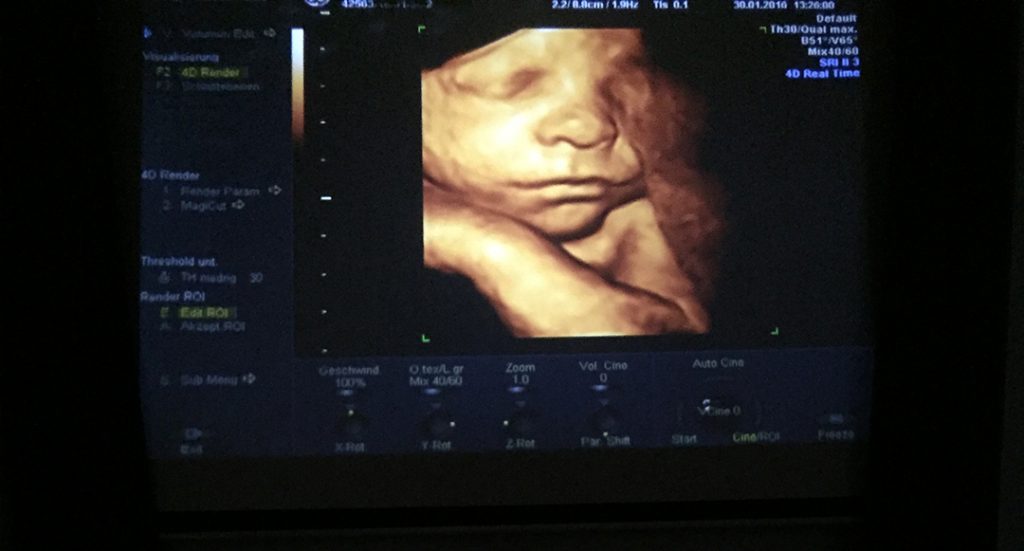

Ein unvergessliches, bewegendes Erlebnis für werdende Mütter und Väter ist ein 3D Ultraschall Bild ihres Babys Im Grunde funktioniert ein 3D-Ultraschall vom Baby nach einem ähnlichen Prinzip wie in 2D: Mittels Schallwellen und ihres zurückgeworfenen Echos errechnet der Sonograf die Entfernung des Gewebes von der Körperoberfläche.

Wie wird ein 3D-Ultraschall durchgeführt und wie ist die Wirkungsweise? Im 3D Ultraschall-Verfahren kann man sehr deutliche Strukturen und Formen erkennen Woman & Health bietet eine innovative 3D Ultraschall-Technologie an, die - durch die Verwendung virtueller Lichtquellen - extrem realistische Bilder des Babys ermöglicht. Da der 3D Ultraschall häufig nicht medizinisch relevant ist, müssen die Kosten in der Regel selbst getragen werden

3D Ultraschall, Schwangerschaftsbetreuung Woman & Health, 1010 Wien. 4D Ultraschall - Ähnlich wie 3D, zeigt jedoch bewegte Bilder in Echtzeit an Bei guten Schallbedingungen können wir so praktisch die ersten Fotos des ungeborenen Kindes anfertigen